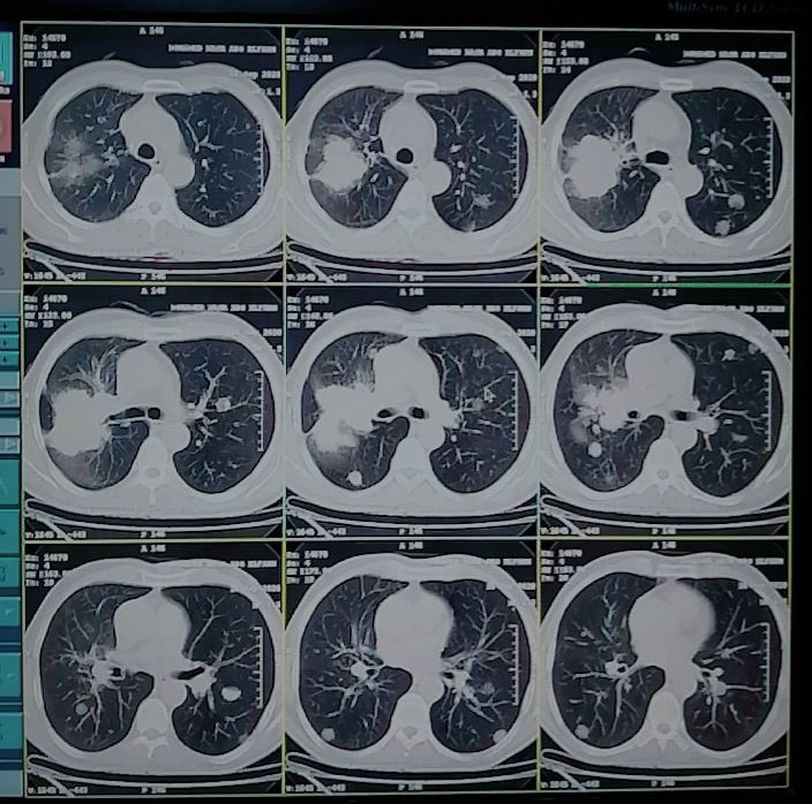

Chest pain SOB Difficulty breathing Male 61Y

Pneumonia